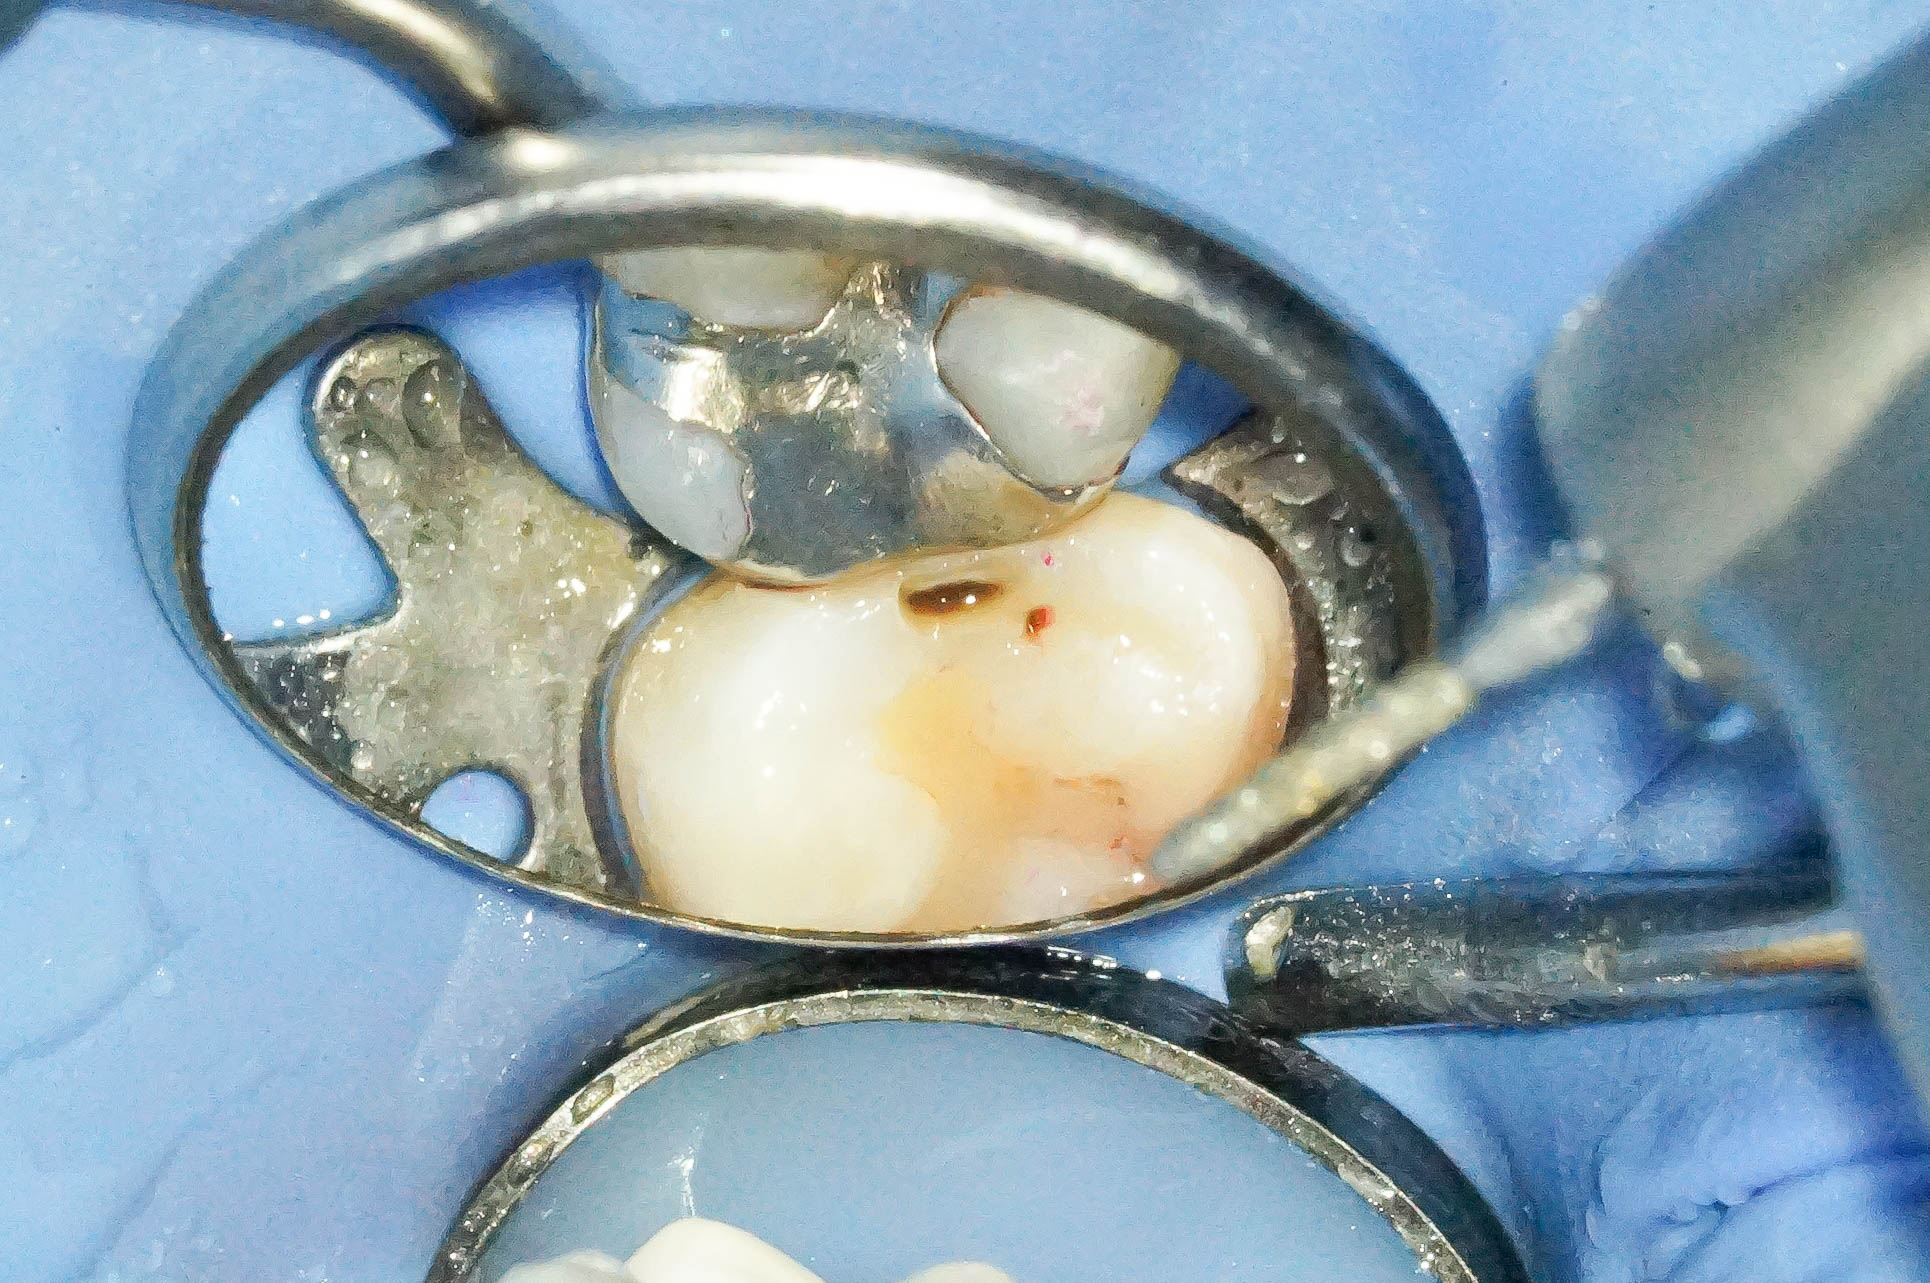

歯肉縁下ダイレクトボンディングを行った症例治療方法01

治療前の写真です。

他院でされたコンポジットレジンですが、フチの部分が黒くなっていたりと、

普段よく見かける一般的なコンポジットレジン修復の痕跡が見受けられます。

そして難易度は高いですが、その部位にラバーダムを設置します。

ラバーダムがなければ処置部位は血まみれ、唾液まみれで繊細な治療ができません。